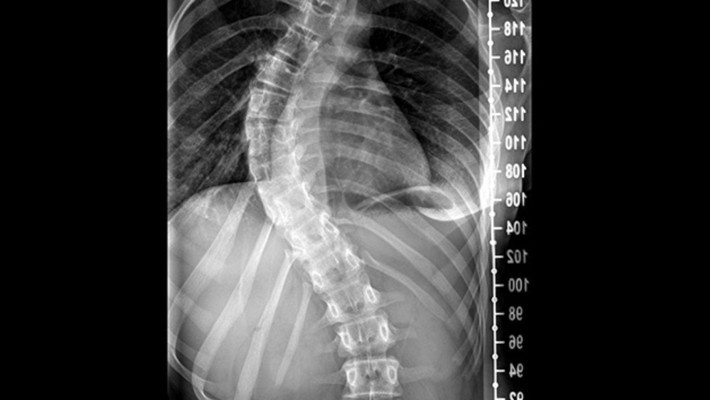

Skolyozun omurganın orta hatta bulunması gerekirken sağa veya sola S ya da C şeklinde eğilmesi ile ortaya çıkan bir rahatsızlık olduğunu bildiren Dr. Yüksel, eğriliğin yalnızca yana değil, öne-arkaya ya da kendi ekseni etrafında rotasyonel şekilde de gelişebileceğini aktardı. Röntgen görüntülerinde ölçülen COBB açısının 10 dereceyi aşması durumunda bireylere skolyoz tanısı konduğunu belirtti.